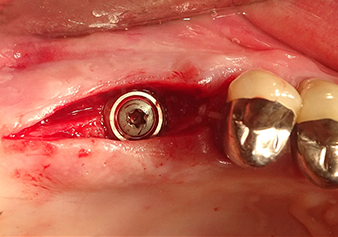

L’insert I2A (diamètre 2,0 mm) est ensuite utilisé pour perforer le plancher sinusien par intermittence et à la plus petite échelle possible. Cette méthode piézochirurgicale spéciale garantit que la membrane de Schneider n’est pas endommagée. Quand le Z25P est utilisé, la membrane est déjà légèrement relevée sous l’effet du fluide de refroidissement délivré via la pointe de l’insert (Fig. 3). Seulement 50 % du fluide de refroidissement sont éjectés afin d'éviter une pression élevée sur le site implantaire.

Préparation et augmentation du site implantaire

Après un contrôle intermédiaire (Fig. 4), une étape de préparation ultérieure est exécutée (Fig. 5). Puis on utilise l’insert Z35P hydraulique pour relever la membrane vers la position souhaitée (Fig. 6 et 7). Ensuite, une préparation piézochirurgicale supplémentaire est pratiquée sur le site implantaire, en utilisant pour terminer un burin rotatif et une fraise à épaulement jusqu’à 4,8 mm de diamètre d'implant. Avant l’insertion de l'implant, le matériau d’augmentation (taille de particules env. 0,8-1,6 mm) est introduit sous la membrane de Schneider (Fig. 8).